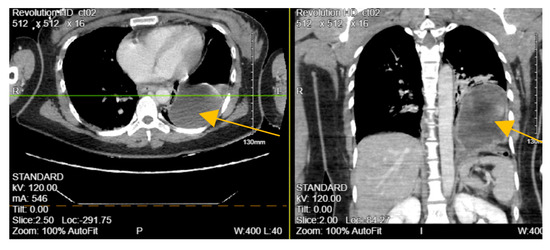

A 28-year-old Asian female with an unknown past medical history was brought by EMS as a pedestrian struck vs. jumped in front of a car at a high rate of speed. She was thrown onto her left side. The initial GCS was 10. On arrival at the ED, the patient was spontaneously moving but mumbling incoherently. Vitals were remarkable for tachycardia, tachypneic, and hypoxia. BP was 136/107 mmHg. The primary survey was notable for deformity of the left forearm and dilated unreactive left pupil. A portable pelvic ultrasound revealed a pelvic fracture. Chest ultrasound showed elevation of the left hemidiaphragm and comminuted diaphyseal fracture of the left humerus with major fragments. CTA of the neck showed C5-C6 with 3 mm posterior subluxation, irregular narrowing of the right vertebral artery extending from C5 to 7, and nondisplaced coracoid fracture of the left scapula. CT chest with contrast (Figure 2) revealed a distended stomach with air fluid in the left hemithorax concerning a closed loop obstruction. eFAST was negative for pericardial fluid. CTAP was consistent with CT chest findings including grade 4 splenic injury with contrast extravasation, grade 3 left renal injury with perinephric collection, and multiple pelvic fractures. The patient became hemodynamically unstable and was emergently taken to the operating room (OR) for exploratory laparotomy. The stomach was successfully reduced into the abdominal cavity from the thorax and on exploration, the diaphragm was noted to have a 6 cm defect, which was repaired with 2-0 ethibond in interrupted fashion with a total of 8 stitches. The patient also underwent splenectomy due to pulsatile red blood extravasation. On the same admission, neurosurgery performed anterior cervical discectomy and fusion and open reduction internal fixation (ORIF) of open humerus fracture and pelvic fracture. Two days after admission, she was taken back to the OR for repair of liver capsular laceration and facial closure. The patient was discharged on postoperative day 47 in stable condition. CXR and CT-A/P were consistent with left TDI. Hence, in this case, blunt TDI was confirmed at laparotomy and repaired. The recorded ISS was 41.

Figure 2.

CT of the chest with contrast showing distended stomach with air and fluid in the left hemithorax (orange arrow), diaphragmatic defect, and grade IV splenic injury parenchymal laceration greater than 3 cm.